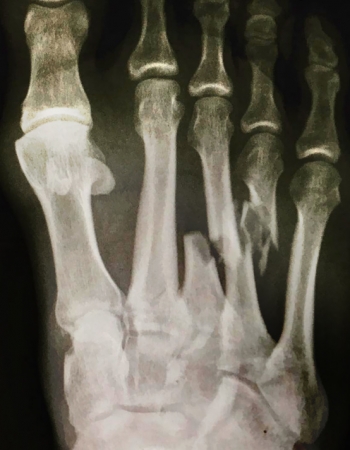

Tuesday 18 July 2017 Eina! Kelly Slater snapped three bones in his foot surfing aptly named Boneyards in cranking J-Bay yesterday and is on a flight home for surgery. Photos Sean Thompson and WSL

He posted dejectedly on Instagram that surgery and a six week holiday were in order after snapping three bones that will require some delicate work and some metal reinforcement.

"You ever folded your entire foot backwards? If you try it sometime, this is what it might look like. I pulled into a barrel this morning and the whitewash bounced the board back into my foot as I hit the closeout, taking all the pressure into the metatarsals. Kinda like smashing my foot with a big hammer as hard as I can. Sorta feels like I'm giving birth out of my foot right now!

"I'm guessing surgery and 6 week holiday is in order. Not looking forward to 30 hour flight home before surgery though. Ouch! It sucks but so many people deal with such horrible things around this world everyday that a broken foot is pretty minor in the scheme of things. Sometimes a bad thing is a good thing. I'll make the best of my time off. #ThatsGonnaLeaveAMark #INeedElephantTranquilizers," he wrote on Instagram.